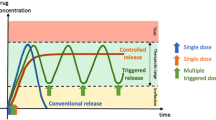

Mutable devices and dosage forms are capable of self-transforming their shape, property or functionality when exposed to non-mechanical external stimulus, such as heat, pH, light, moisture, electric or magnetic fields, or ion composition [1]. The capacity to induce dimensional, morphological and mechanical changes upon contact with non-mechanical external triggers is especially considered a promising characteristic for the fabrication of minimally invasive implants or residence devices in targeted areas of the body [2]. By utilizing temporary, smaller, shapes for easier administration (e.g., via catheters, syringes, or even oral ingestion), these devices can then undergo a controlled transformation upon reaching their target, ensuring sustained drug release within the targeted area [3]. While established residence devices such as intragastric balloons for obesity and stents show clinical success, many rely on procedures like endoscopies, surgeries, and anaesthesia, underscoring the demand for minimally invasive alternatives [4, 5].

The adaptation of stimuli responsive materials—namely, shape memory polymers (SMPs), stimuli-responsive hydrogels, or liquid crystal (LC) polymers—in 3D printing has allowed for the printing of stimuli responsive, mutable, structures with tuneable morphologies [2, 3]. The term 4D printing (4DP) was introduced to encompass all 3DP technologies that produce objects capable of having programmable time-dependent alterations [15]. The increase in utilisation of conventional 3D printing technologies for 4D printing has been seen in a myriad of fields. Notable applications of 4D printing include heat-activated flexible temperature sensors [16], cardiac patches [17], drug eluting stents and implants [18], scaffolding for tissue regeneration [2], hydrogel-based wound dressings for simultaneous monitoring and drug delivery [19], biocompatible smart scaffolds [20], and self-folding hydrogel scaffolds [21]. Volumetric printing has shown merit in pharmaceutical sciences for preparing simple oral dosage forms at ultra-rapid speeds; however, other potential applications and the versatility of this technology have largely been unexplored, particularly its ability to create mutable drug delivery devices and dosage forms.

This study focuses on two vat photopolymerisation technologies: DLP (digital light processing) and volumetric printing, comparing their efficacy and suitability for fabricating mutable hydrogel-based drug-eluting devices with potential application as gastro-retentive drug delivery systems. Hydrogels, due to their inherent mechanical properties, pose minimal risk of tissue penetration, making them well-suited for gastro-residence purposes [22]. These mutable drug-eluting devices were successfully fabricated using both vat photopolymerisation technologies, and studies were conducted to comparatively investigate their swelling characteristics, drug release kinetics, and physicochemical properties. This comparative study investigates the potential of volumetric printing in creating these dynamic drug-eluting devices, evaluating its performance against the conventional DLP approach.